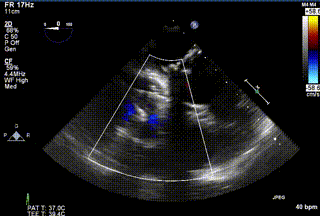

2021年12月24日,復旦大學附屬中山醫(yī)院葛均波院士團隊成功應用LuX-Valve Plus為一例極重度三尖瓣反流(TR)合并房顫、房缺的患者完成了經血管三尖瓣置換術,這是在前基礎上,本周完成的第三例經血管三尖瓣置換手術,葛均波院士、周達新教授等與心外科魏來教授、賴顥教授,心超室的潘翠珍教授、李偉教授及麻醉科的郭克芳教授共同完成了本周手術,均獲得圓滿成功!患者術后超聲顯示無TR,臨床癥狀明顯改善。本周手術的成功也為LuX-Valve Plus救治性臨床研究添上了濃墨重彩的一筆。

三例患者入院后,葛均波院士團隊周達新教授、潘文志教授、張源博士、陳莎莎博士及心超室的潘翠珍教授、李偉教授對患者的情況進行詳細評估和討論,最終決定為三例患者選擇LuX-Valve Plus40mm、50mm和50mm型號的瓣膜進行手術治療。手術后即刻拔除氣管插管,術后患者三尖瓣反流癥狀得到顯著改善,復查心超結果顯示人工三尖瓣瓣膜支架固定穩(wěn)定,瓣葉關閉形態(tài)未見異常,未見明顯反流。